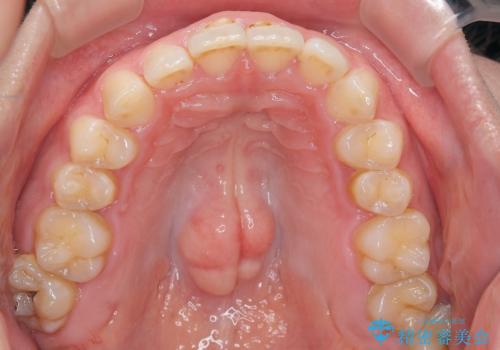

- 下の歯のがたつきを主訴に来院されました。

下の歯のがたつきと右の奥歯の噛みあわせ改善するために治療計画を立てることにしました。

右側臼歯部の咬合改善のために、臼歯部のみ部分的なワイヤー矯正を行い、咬合改善がみられてからインビザラインにて全体的な矯正を行なっていく治療計画を立てました。